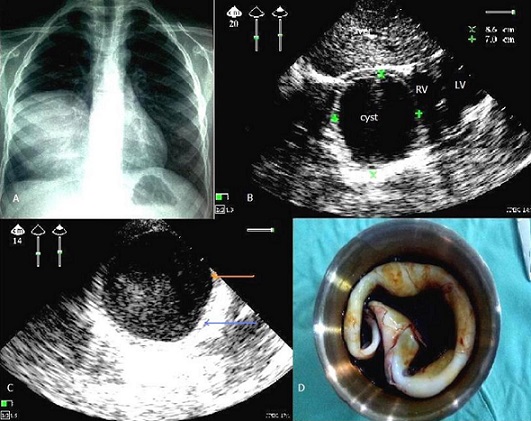

Pulmonary hydatid cyst in a child of 11 years detected by ultrasound lung

Pulmonary hydatid disease is the most common location of hydatid disease of the child. Echinococcus granulosus responsible for this infection is known in the achievement of certain animals such as dogs, man is an accidental intermediate host in parasite's life cycle. The lung is infested after crossing the liver filter, either directly by the lymphatics. The cyst is composed of a germinal membrane, and a pericyst (pulmonary inflammatory response of the host.) It is clinically manifested by cough, chest pain, fever, hemoptysis and hydatid vomica but sometimes asymptomatic incidental finding. Chest radiography is strongly suspected the diagnosis, Partner at thoraco abdominal ultrasound, allows in most cases easy diagnosis. Lung ultrasound is unfortunately largely neglected in this context then it is the key to make this diagnosis without the use of chest CT. Recently Fortia M et al in 2006 have published a new specific sign ultrasound for the wall of hydatid cyst pulmonary: a double layered border in univesicular and double layered internal septum in multivesicular pulmonary echinococcal cysts is a reliable indicator of pulmonary echinococcosis, with a specificity near to 100%. And therefore ultrasonography should not be overlooked for the diagnosis of pulmonary hydatid cysts. To the presence of this sign, is easily eliminates differential diagnosis in the child include: chest neuroblastoma, lung abscess, cystic duplication of the thoracic esophagus, bronchogenic cyst, and pulmonary sequestration. We report a clinical case in a child of 11 years, with notion of contact with dogs, admitted for atypical chest pain with hemodynamic stability in whom a chest X-ray showed a right basal opacity limited, the ECG was normal , thoracic ultrasound showing anechoic image with posterior reinforcement, well limited, with duplication of the wall (germinal membrane hyperechoic and reaction of the host) pathognomonic of hydatid cyst, right basal pulmonary, diameter 8.6/7 cm, type I according to the sonographic classification Gharbi. The heart and abdominal ultrasound (liver, spleen, kidney) without abnormalities, the hydatid serology was negative, the child was operated under general anesthesia, Leaving the hospital six days later without sequelae.